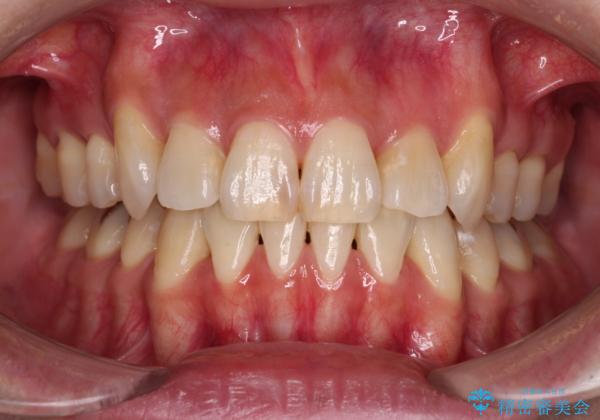

- 八重歯や前歯のデコボコを気にして来院された患者様です。

目立たない装置を希望されたので、上顎が裏側装置のハーフリンガルを選択し、上下左右の小臼歯(計4歯)を抜歯して矯正治療を行うこととしました。

補助装置を併用することで、八重歯を速やかに改善し、治療期間の短縮を図ることとしました。

デコボコが強い一方で出っ歯ではなかったため、抜歯したスペースを容易に閉じることができ、短期間での治療となりました。